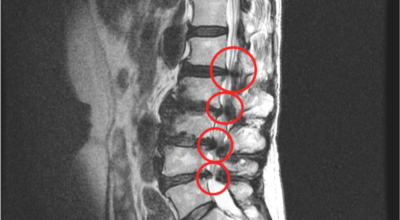

요추관 협착증은 척추 내 신경이 지나가는 통로가 좁아지는 현상으로 기인해서 신경이 눌리면서 이에 따른 여러가지 증상을 유발하는 질환을 의미해요.

허리 협착증은 척추관이 좁아지게 되면서 신경을 압박하게 되어 허리통증과 또한 다리에도 여러가지 증상을 일으키게 되는데, 발생 원인은 주로 노화로 인한 퇴행성 변화가 많았지만 요즈음는 옳지 않은 자세로 오랫동안 앉아있는 사람들이 많아지면서 생기는 경우도 많아졌으며, 선천적인 요인으로 나타나는 경우도 있답니다.

일상생활에서 허리 척추에 무리를 주는 행위가 반복적으로 행해질 경우 허리 뿐만 아니라 주변 근육과 인대의 퇴행이 빨라질 수 밖에 없어요. 허리 협착증의 경우 허리를 뒤로 젖히면 통증이 심하게 나타나지만 허리를 굽히면 척추관이 일시적으로 넓어지는 영향으로 통증이 줄기 때문에 자연스럽게 아프지 않은 자세를 하다보니 허리가 점점 굽는 자세를 만들 수 있어요.